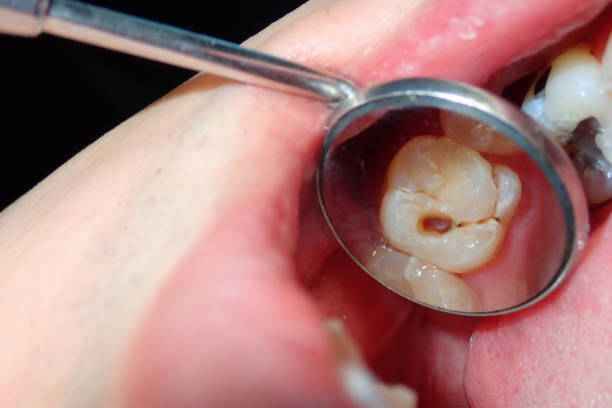

ما هي أسباب تسوس الأسنان ؟

يُعد تسوس الأسنان من أكثر المشكلات شيوعًا، وهو نتيجة تفاعل معقد بين البكتيريا، والعادات الغذائية، ومستوى العناية الفموية. في عيادة اسنان الدمام، يتم التركيز على فهم الأسباب الجذرية للتسوس للحد من انتشاره. وتشمل أبرز الأسباب:

- تراكم البلاك البكتيري على سطح الأسنان نتيجة ضعف التنظيف اليومي وعدم استخدام الوسائل المساعدة كخيط الأسنان.

- الإفراط في تناول السكريات والنشويات التي تُعد بيئة مثالية لنشاط البكتيريا المسببة للتسوس.

- قلة إفراز اللعاب أو جفاف الفم، مما يقلل من قدرة الفم على معادلة الأحماض.

- إهمال الفحوصات الدورية التي تكشف عن التسوس في مراحله المبكرة.

- ضعف مينا الأسنان نتيجة عوامل وراثية أو نقص بعض المعادن.

- العادات الغذائية الخاطئة، خاصة تناول الوجبات السكرية قبل النوم.